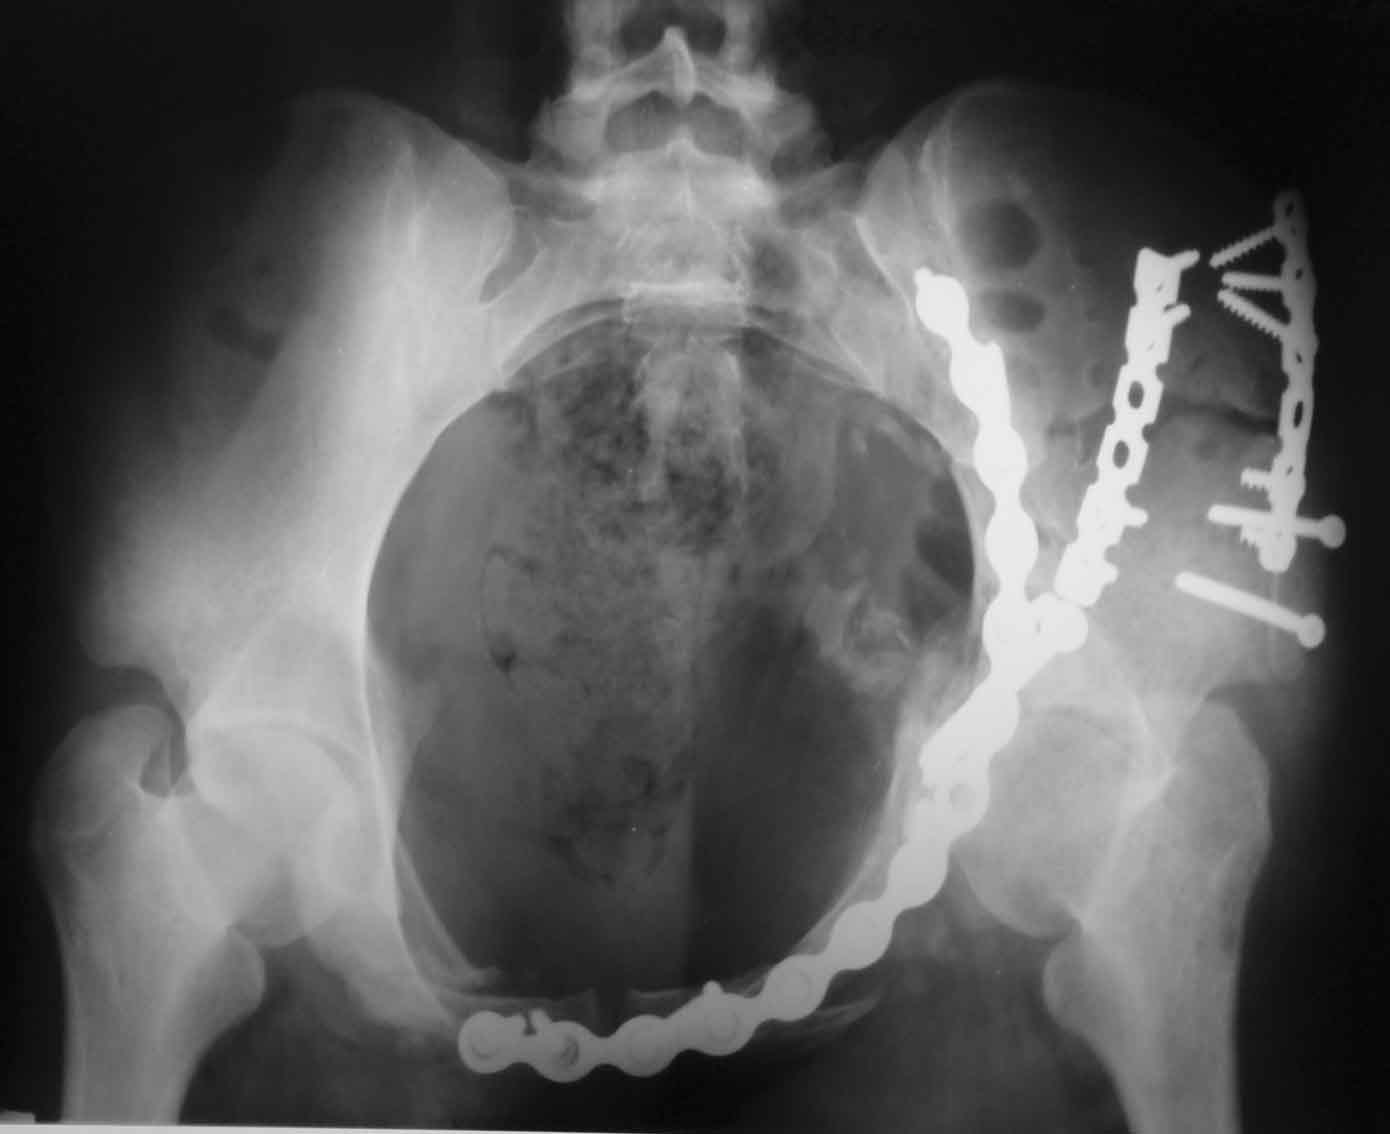

подвздошная

По всей видимости, вы имеете в виду канюлированный винт, который проецируется на вертлужной впадине. Та вот, он проведен не через лонную, а седалищную кость. Вертлужная впадина абсолютно интактна. Это хорошо видно на проекции inlet.